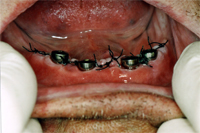

Am 2. Oktober 2006 wurden unter Aufklappung vier Implantate gesetzt. Eine Woche später kommt der Patient zur Nahtentfernung (Abb. 1). Die postoperative Schwellung ist verschwunden und die Nähte werden entfernt. Die Einheilkappen sind für die Abdrucknahme vom Implantat entfernt (Abb. 2). Mit der bestehenden Prothese wird nun der Abdruck genommen. Noch gleichentags fertigt der Techniker den Implantatsteg an, den ich im Mund provisorisch festschraube (Abb. 3).